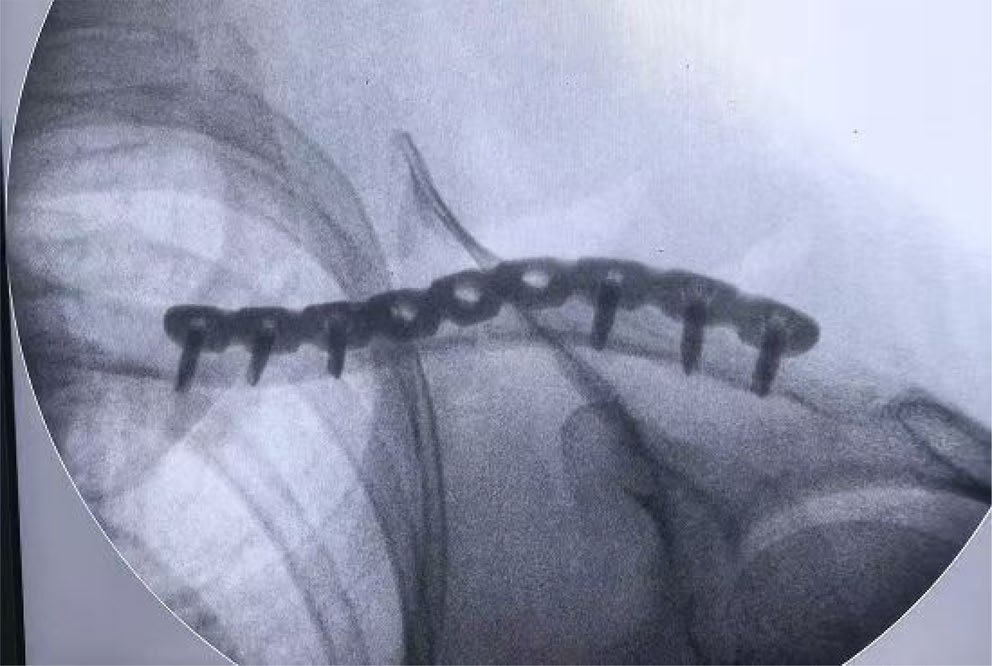

6、术后X线片

1、锁骨MIPO:微创钢板接骨术。

2、插入导向器组装的接骨板。(B)沿着锁骨上边缘插入接骨板

3、植入锁定螺钉

4、术前X线片,术后8周随访时的X线片,术后瘢痕。